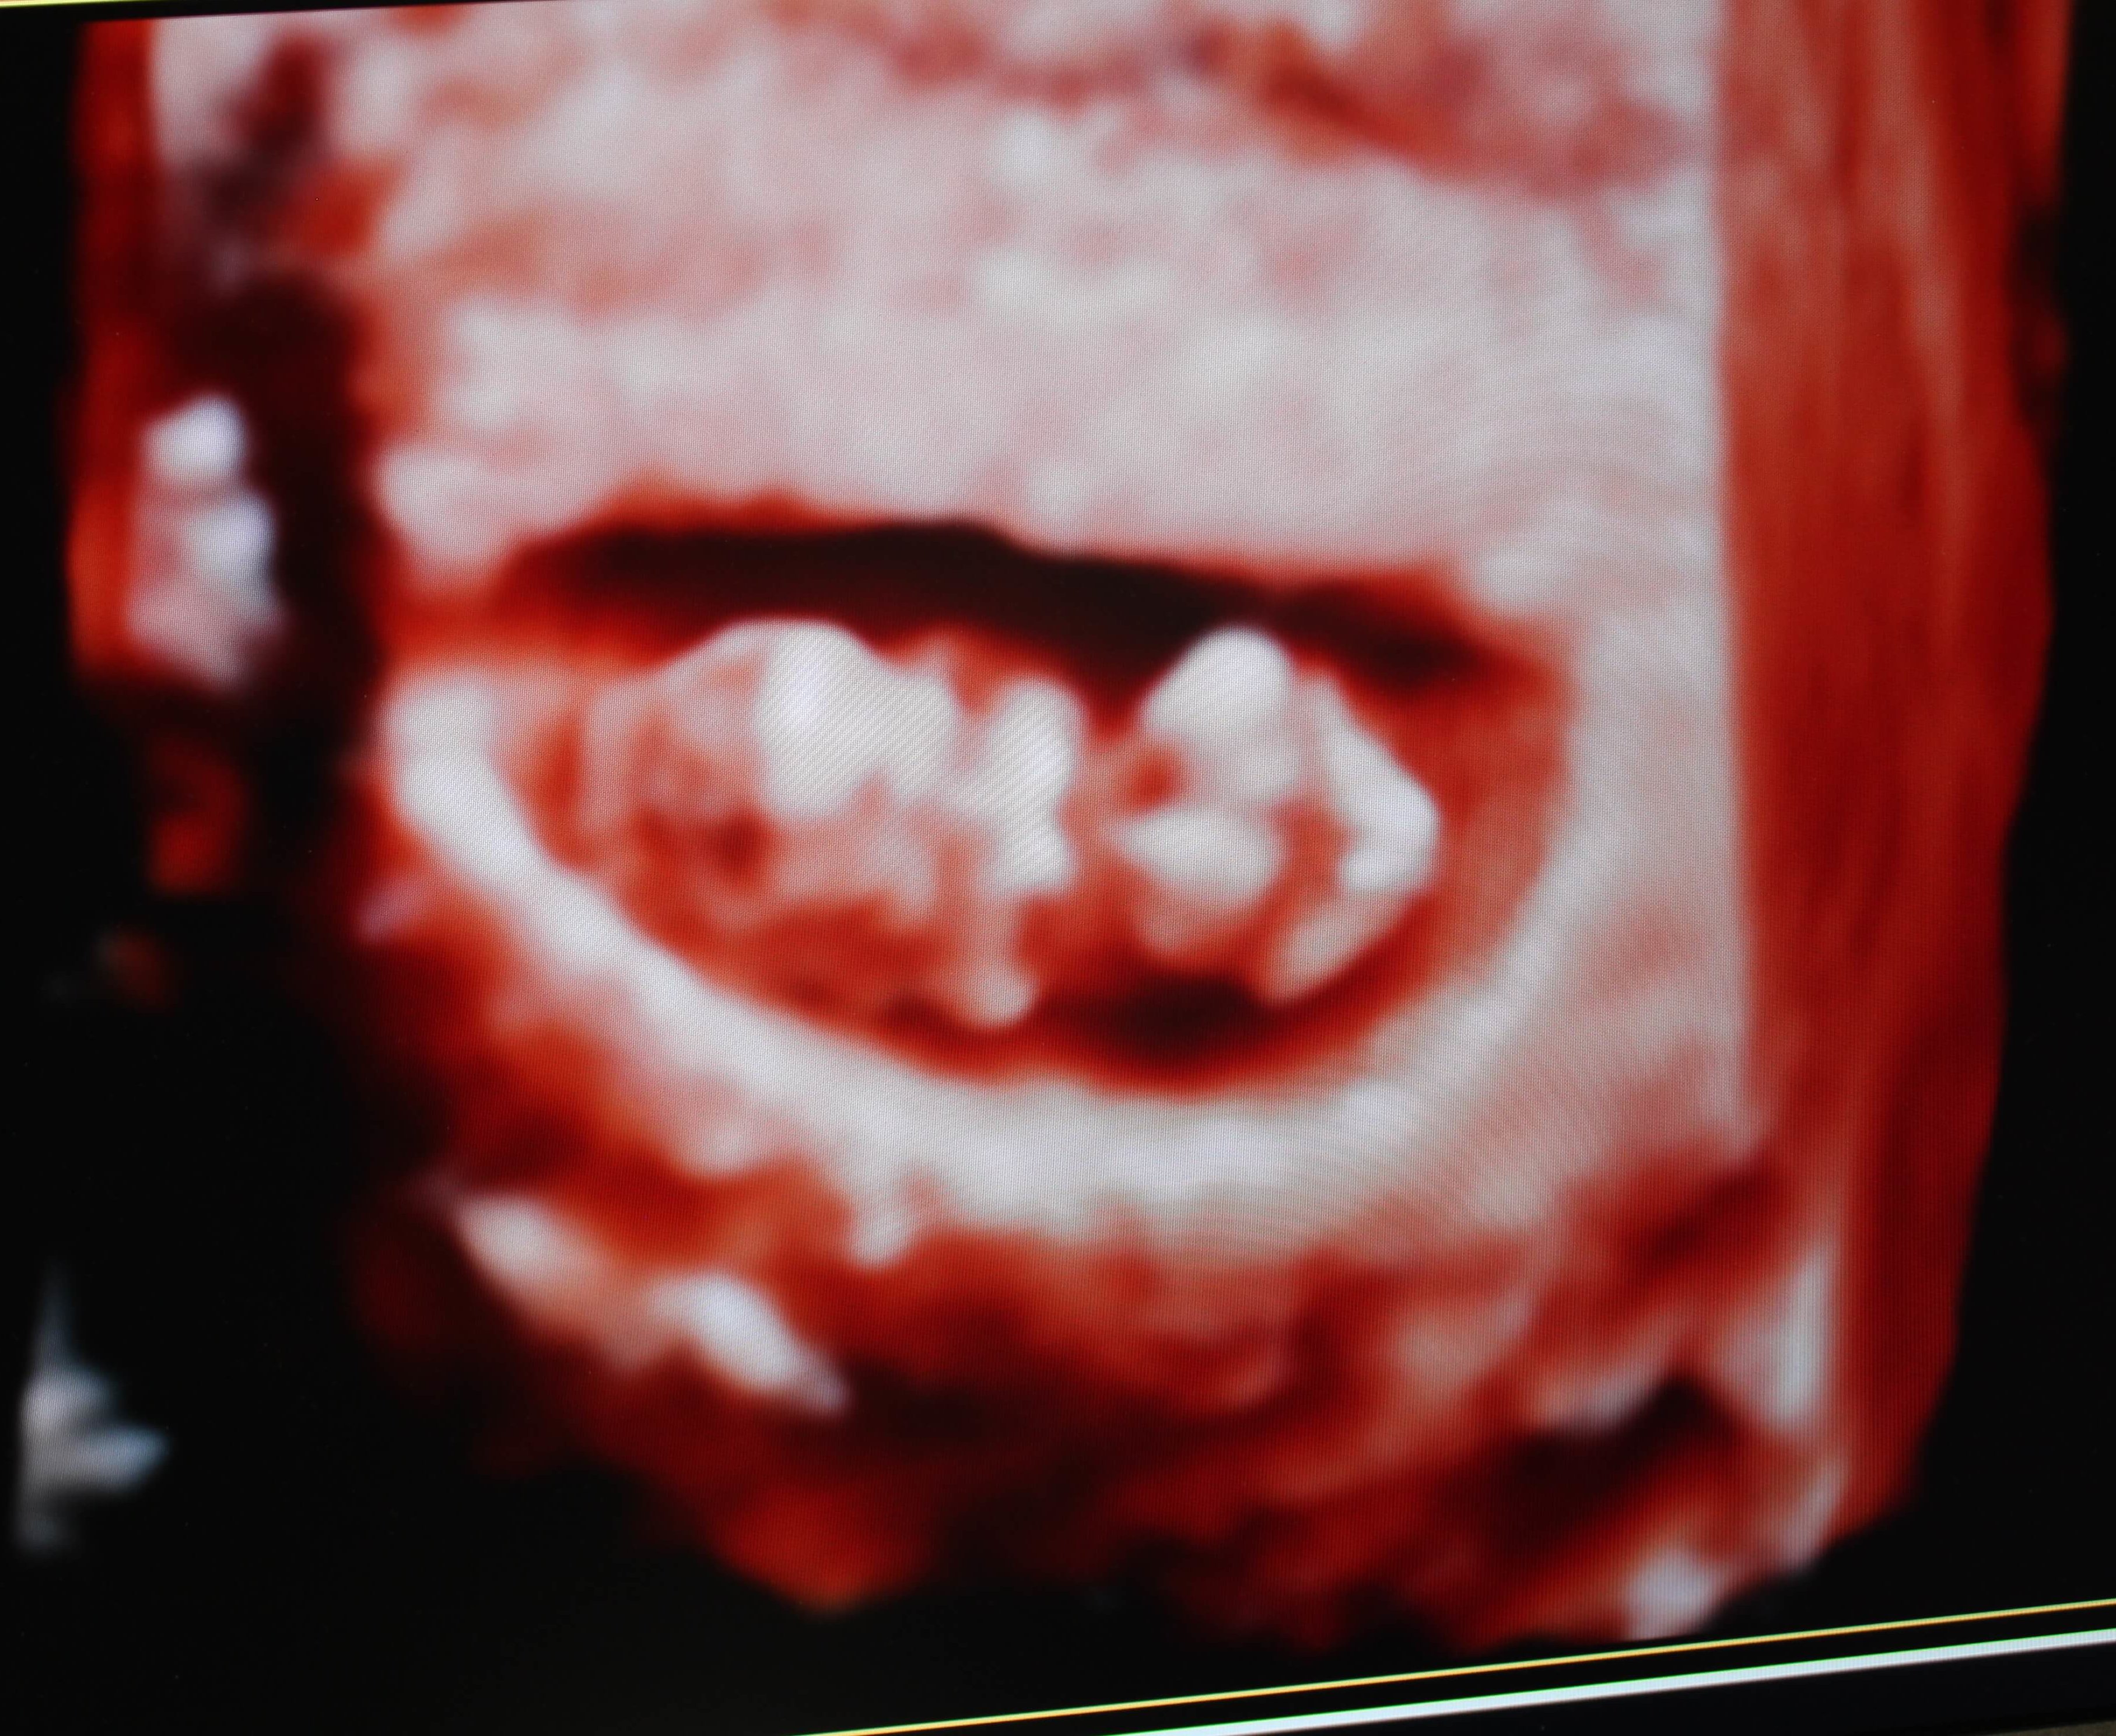

CUTLINE: Pictured are ultrasound images from current patients at HCMC Paris Women’s Center. HCMC Paris Women’s Center is pleased to offer state-of-the-art, in-office Ultrasounds to patients early in their pregnancies with amazing images and quick results.whit

Ultrasound imaging uses sound waves to produce pictures of the inside of the body. It is painless and the best way to see what is going on with the development of the pregnancy. Most initial ultrasounds are completed after the 5th week of pregnancy to ensure that the gestational sac is developing and to determine if there is more than one baby. You want these pictures to be crystal clear and with the technology used at Paris Women’s Center, you will be more than pleased with the results.

“It’s awesome because it has the capability to send patients pictures digitally through text, USB drive, or CD,” said Stefanie H., Radiologic Technologist at Paris Women’s Center. “It also has TrueVue, which lets us manipulate a 4D image live while scanning OB or GYN exams.”

“Having early ultrasounds and screenings with Dr. Evans provided me reassurance early in the pregnancy,” said Crawford. “I felt seeing my baby developing at nine weeks gave an incredible amount of joy about the life growing inside of me. Dr. Evans and the staff at the HCMC Paris Women’s Center have treated me like family. They have always treated me with the upmost respect, and have made me feel comfortable during every visit. I would recommend any woman to try out the HCMC Paris Women’s Center. Once you go, you will want them to be the staff caring for you and your baby.”